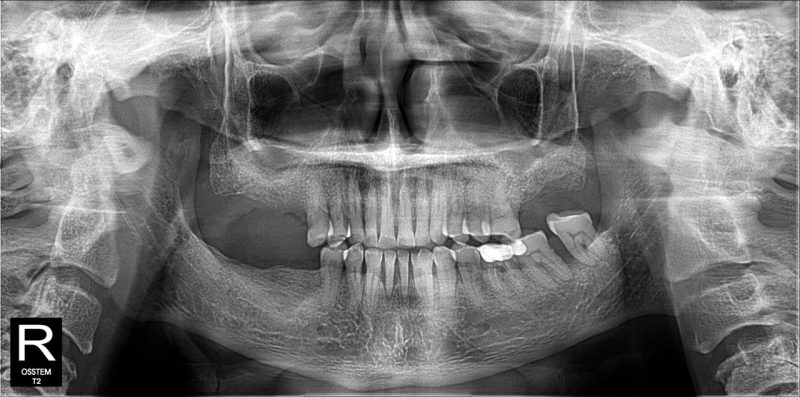

“Tưởng chừng chỉ là vài chiếc răng bị mòn, tụt nướu hay mất răng lâu năm… nhưng những vấn đề tưởng chừng đơn giản đó lại âm thầm ảnh hưởng lớn đến sức khỏe, khả năng ăn nhai và cả sự tự tin mỗi ngày.” Đó cũng chính là tình trạng mà chú Nguyễn Văn Bé trước khi tìm đến Nha khoa SGC.

Đặt tiêu chí tối ưu, an toàn và phù hợp, đội ngũ bác sĩ chuyên môn tại SGC đưa ra giải pháp bao gồm: cấy ghép 4 trụ Implant Neodent vững chắc để khôi phục các răng hàm đã mất và bọc 24 răng sứ thẩm mỹ cao cấp.